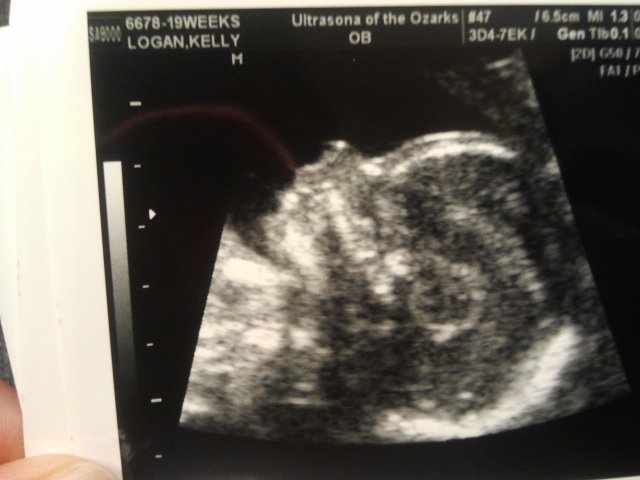

Look how teeny tiny but still has all the feautures of a full term baby at only 19 weeks! How could

anyone ever doubt that this is a LIFE!